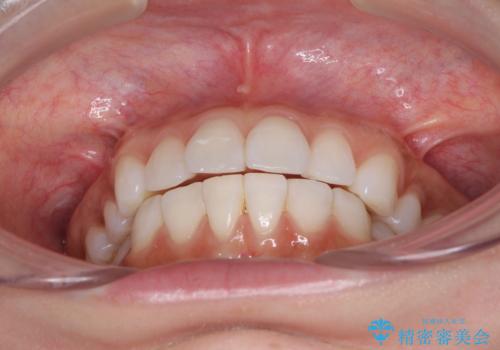

矯正治療の後戻り インビザラインによる再矯正治療

- 以前ワイヤー装置にて行った抜歯矯正の後戻りを気にして来院された患者様です。

前歯のデコボコにより、やや口元が突出した印象となっていたため、口元も引っ込めることとしました。

上下顎前歯に積極的にIPR(歯と歯の間を削る)を行い、インビザラインを用いて治療していくこととしました。

デコボコが解消されるのはもちろんのこと、突出感のあった前歯を引っ込めることができ、患者様には大変満足していただきました。